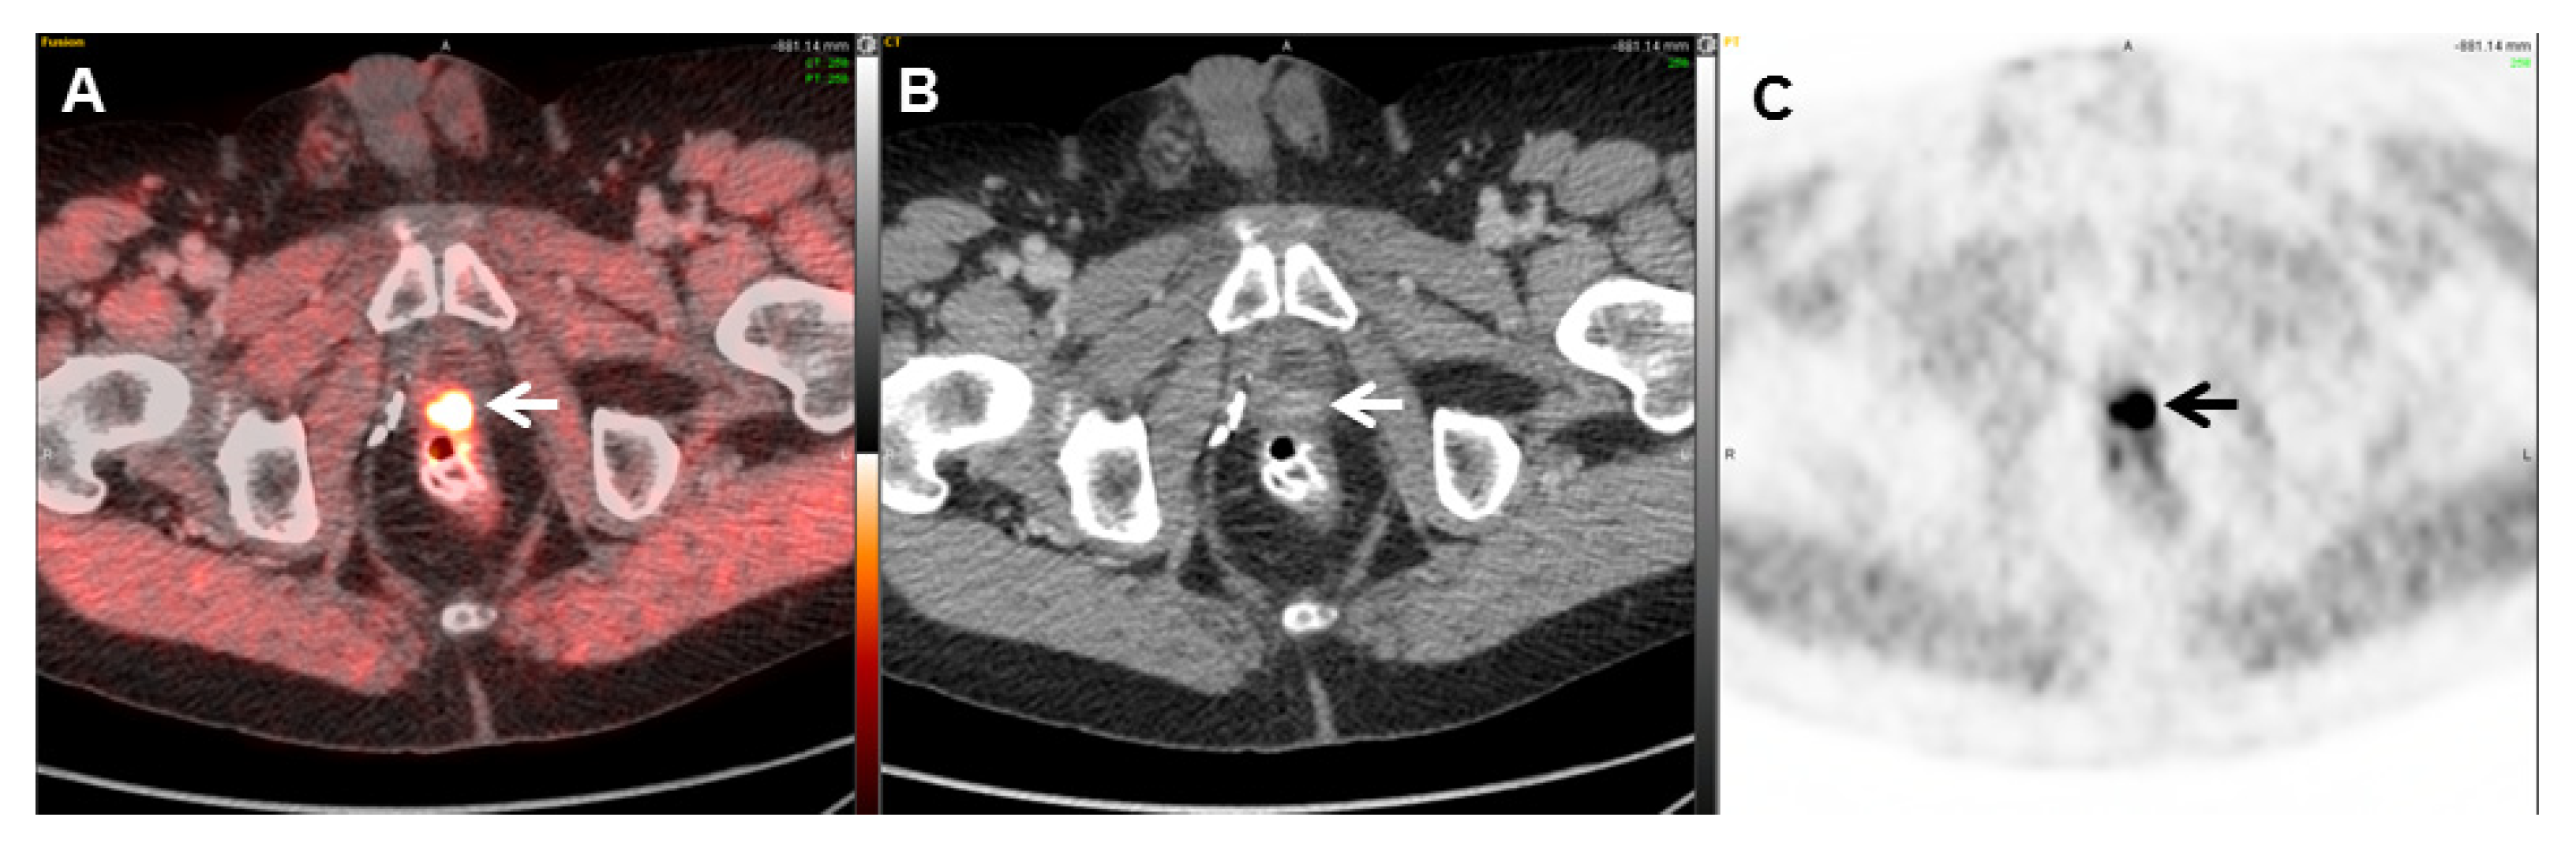

2.5.2. 64Cu-DOTAGA-PSMA